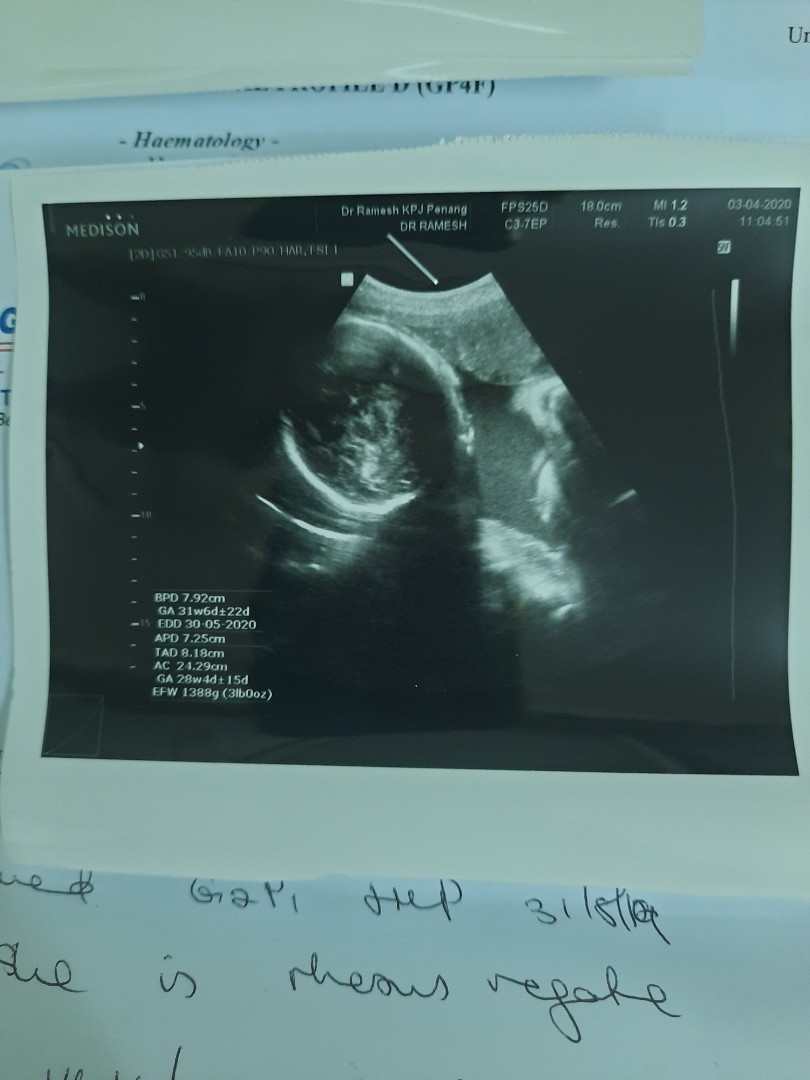

มีคนมาว่าแม่นับวันผิดบ้างหละ คลอดก่อนกำหนดบ้างหละ คือรูปนี้นานแล้ว ตอน16wแล้ว แม่ลงนานแล้วนะค้ะ ตอนนี้ก็ 28wละจ้าา บ้านนี้กำหนดคลอด28มิ.ย.63 เพศชายจ้า?